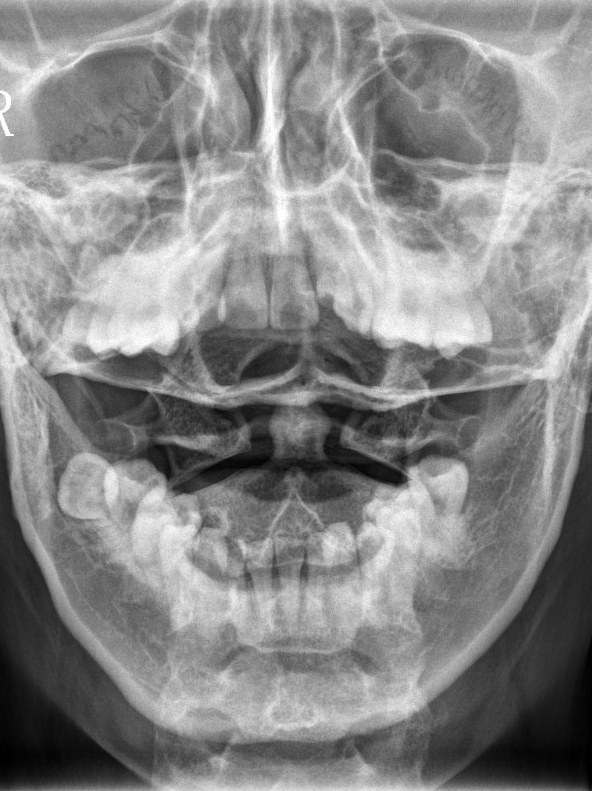

【影像】广州中医药大学深圳医院MR示:C5-6间盘膨出,L4-5间盘突出。X线示颈椎反弓伴侧弯,寰齿侧间隙右宽左窄,寰椎左侧侧块小。

【诊断】颈椎病;寰枢椎半脱位;